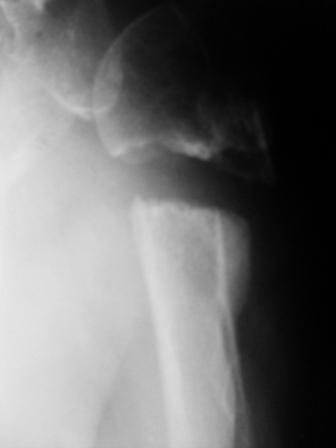

Уважаемые коллеги! Госпитализирована больная 51года. Травма - перелом

хирургической шейки плеча в феврале 2009г. Лечилась по месту

жительства Лонгетной гипсовой повязкой. На фоне сформировавшегося

ложного сустава работает маляром. Объем движений и сила естественно

ограничены. При обсуждении тактики лечения возникли разногласия по поводу вида остеосинтеза и его

целесообразности.